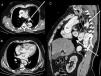

Fifty-seven-year-old male with a past medical history of high blood pressure and hiatal hernia admitted to the ER with clinical signs of syncope and chest pain. He is diagnosed with a Stanford type A aortic dissection and immediately referred to urgent surgery. After the intervention, the patient is admitted to the Intensive Care Unit. In order to guarantee enteral nutrition a nasogastric tube is inserted with difficulties when trying to move the tube forward. Its positioning is verified through the use of contrast and its malposition is eventually confirmed (Fig. 1). The thoracic coronary CT angiography shows a dissection-induced aortic hematoma causing an extrinsic esophageal compression with progressive tapering and dilatation prior to the obstruction (Fig. 2). Eventually, the patient requires endoscopic implantation to resolve the esophageal stenosis.

Thoracoabdominal CT scan. A. Pre-stenotic axial image showing the esophageal dilatation and aortic dissection. B. Axial image of the compression region (white asterisk). C. Coronal imaging showing progressive esophageal tapering.Ao, aorta with image of aortic flap; LA, left atrium; LV, left ventricle; PA, pulmonary artery; RV, right ventricle. White arrow: pre- and post-stenotic esophageal dilatation. White asterisk: esophageal obstruction region.